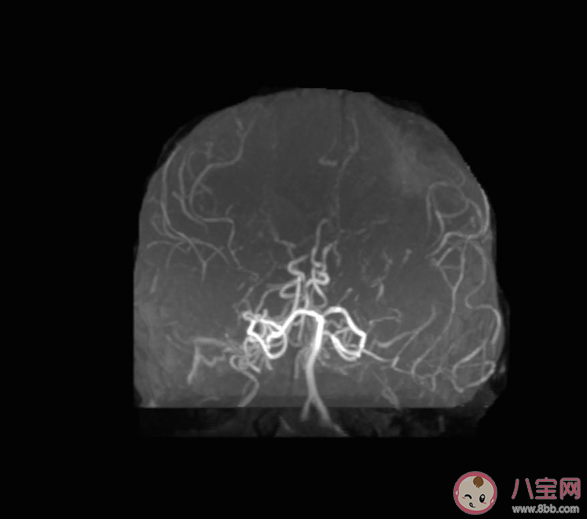

“煙霧病”是一種以雙側頸內動脈末端或其主要分支進行性狹窄或閉塞為特征,并繼發顱底異常擴張血管網形成的一種腦血管閉塞性疾病。煙霧病最初是在日本被發現,由于擴張的腦血管在血管造影時的形態如煙囪里冒出的裊裊炊煙,日語稱為moyamoya,因此被形象地稱為“煙霧病”,也為moyamoya病。

其主要臨床表現為腦出血、蛛網膜下腔出血、腦梗死、部分表現為癲癇、頭痛及認知障礙、反復暈厥。那么如何診斷該病呢,我們稱之為“三A”檢查,即磁共振血管造影MRA、腦血管三維重建CTA、全腦血管造影DSA,以上檢查層層遞進,且DSA是金標準。一旦確診,顱內外血管重建術是其主要治療方法,該手術通過顱內外血運重建改善腦供血,使大腦對于煙霧血管的需求降低,從而降低患者再次發生腦缺血和腦出血的風險,改善患者的預后。